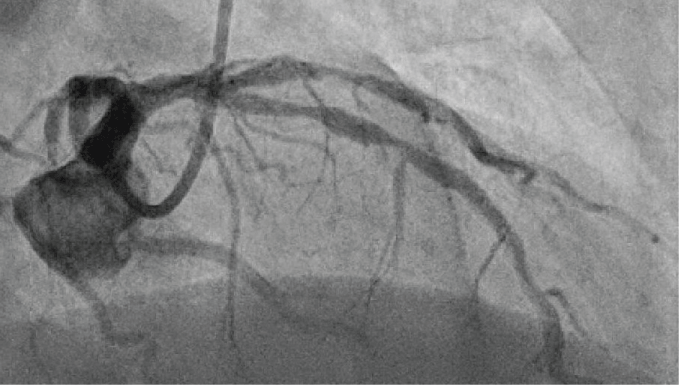

The first patient, a 65-year-old male, presented to our emergency department with unstable angina without troponin elevation for the first time in January 2015. A calcified culprit lesion in the Right Coronary Artery (RCA) was managed by stenting. Staged Percutaneous Coronary Intervention (PCI) of a significant proximal stenosis of the Left Anterior Descending (LAD) was scheduled for March 2015. During this procedure, two drug-eluting stents were implanted in a highly calcified and tight stenosis of the LAD (Figure 1). Significant residual stenosis was observed, which could not be resolved by high-pressure angioplasty at 26 atm with a non-compliant balloon catheter, or even at 35 atm with an ultra-high pressure balloon (OPN NC balloon, SIS Medical, Switzerland) (Figure 2). The stable patient was transferred the next day to a high-volume center for definitive treatment of the lesion by repeat angioplasty or alternatively rotablation of the implanted stent as a bail-out option. During this second procedure, a shorter ultra-high pressure balloon was inflated in the stent to optimize focussed pressure delivery to the resistant area. Pressure was increased slowly into the off-label range > 35 atm, as reported previously [1]. At 40 atm rupture of the balloon catheter occurred, as evidenced by an abrupt drop in pressure in the indeflator (device to in- and deflate PCI balloons). Unusually, the balloon itself remained inflated within the coronary artery, i.e. filled with contrast medium (Figure 3), whereas the rupture had obviously taken place in a more proximal part of the catheter. As the inflated balloon fully occluded the LAD, ST segment elevations were noted on the monitor ECG and the patient began to suffer from angina. When gentle pull was applied to remove the still inflated balloon from the coronary artery, the proximal shaft completely detached from the distal part at the rupture site (Figure 4 and Figure 5). An attempt to puncture the inflated balloon inside the LAD with the stiff end of a coronary wire that was advanced through a microcatheter failed. Removal of the detached and still partially inflated balloon from the calcified lesion was eventually achieved by "jailing" the remaining balloon shaft in the guiding catheter with another balloon inflated at high pressure inside the guide and then carefully retracting the catheter together with the balloon (Video 1). Total ischemia time until successful retrieval was 30 min. Patient recovery was uneventful and without residual wall motion abnormalities at discharge, although the complication led to a significant increase in necrosis markers and stent deployment was still suboptimal.

Figure 2: "Dog-boning" of ultra-high pressure balloon inflated inside the stent at 35 atm. View Figure 2